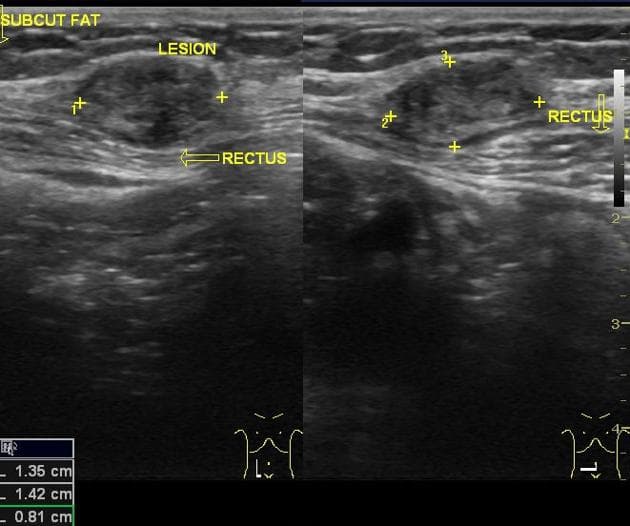

- Tổn thương dạng nang lớn ở vùng chậu bụng bên phải, trên cộng hưởng từ (MRI) tổn thương này tăng tín hiệu ở chuỗi xung T1 và T2, có vách ngăn nội tại.

- "U lạc nội mạc tử cung thường biểu hiện là các nang buồng trứng đơn hoặc đa ngăn, có tăng tín hiệu đồng nhất trên cả chuỗi xung T1 và T2 do chứa sản phẩm máu mạn tính."

- "Dấu hiệu chấm tối trên T2 (T2 shading) trong lòng nang là đặc điểm điển hình của u lạc nội mạc, do lắng đọng hemosiderin đậm đặc."

- "Vách ngăn nội tại và dày thành nang dạng nốt cho thấy tình trạng mạn tính hoặc nguy cơ chuyển ác, cần theo dõi sát."

U lạc nội mạc tử cung, còn gọi là 'nang sô cô la', là một dạng lạc nội mạc tử cung khi mô nội mạc tử cung lạc chỗ bám vào buồng trứng và xuất huyết theo chu kỳ. Trên cộng hưởng từ (MRI), u lạc nội mạc thường có tín hiệu tăng trên cả chuỗi T1 và T2 do chứa máu cũ. Hiện tượng 'mờ tín hiệu trên T2' (T2 shading) – khi tín hiệu giảm dần trên hình T2 – rất gợi ý cho chẩn đoán u lạc nội mạc. Các chẩn đoán phân biệt bao gồm nang buồng trứng xuất huyết, u nang tuyến mề và u tuyến nang nhầy. Tuy nhiên, tín hiệu T1 tăng rõ rệt và vách ngăn nội tại làm tăng khả năng u lạc nội mạc. Chẩn đoán chính xác rất quan trọng để định hướng điều trị, bao gồm điều trị nội tiết hoặc phẫu thuật cắt bỏ, đặc biệt ở bệnh nhân vô sinh hoặc đau vùng chậu mạn tính.